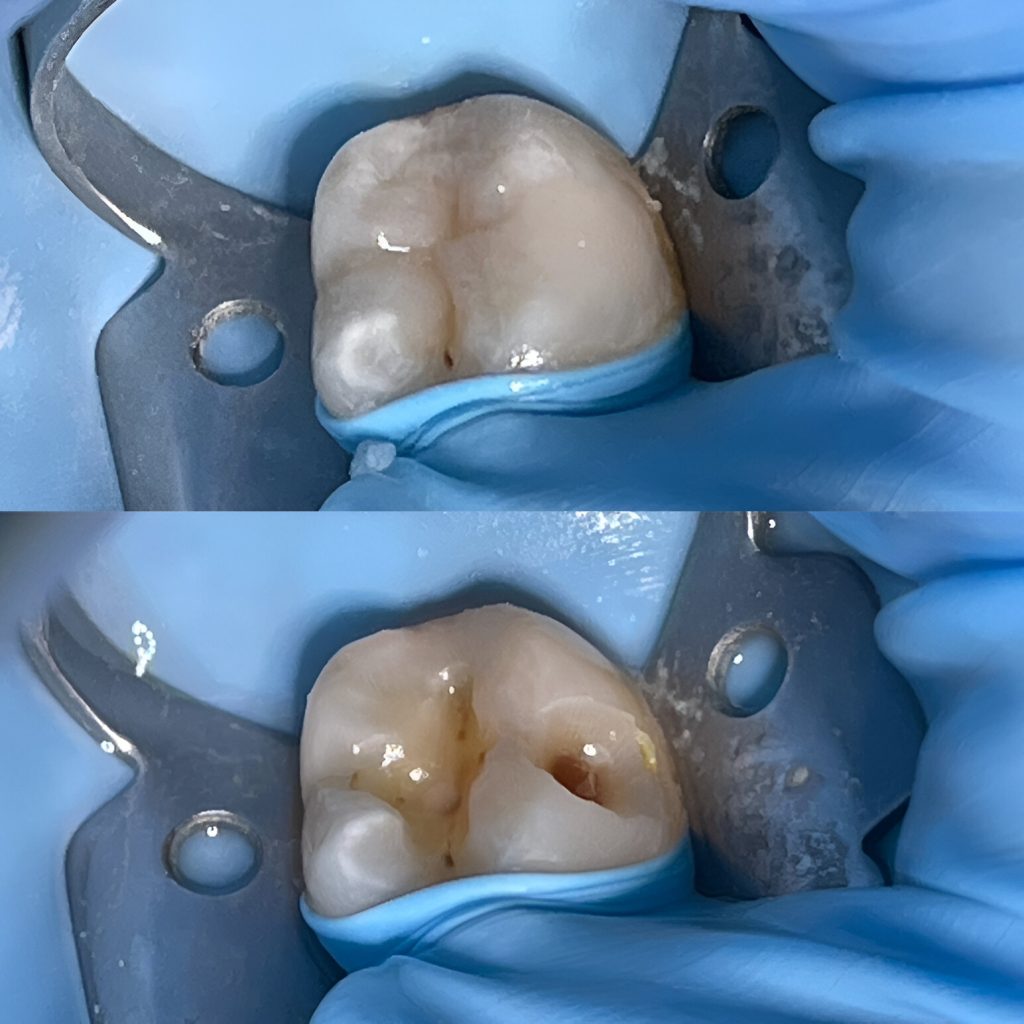

Terapinis gydymas Terapinis dantų gydymas – tai viena svarbiausių procedūrų, skirta suaugusiųjų ir vaikų burnos sveikatai išsaugoti. Šio gydymo metu efektyviai šalinamas dantų ėduonis (kariesas), restauruojami nuskilę ar nulūžę dantys bei keičiamos senos, nehermetiškos plombos. Taip pat atliekamas pleištinių defektų gydymas, padedantis apsaugoti apsinuoginusius dantų kaklelius nuo jautrumo ir tolesnio dylimo. Naudojant modernias medžiagas, atkuriama natūrali danties forma, spalva ir pilnavertė funkcija.Kas yra dantų ėduonis?Viena iš labiausiai paplitusių dantų ligų – dantų ėduonis (dar vadinama kariesu), kuri atsiranda dėl rūgščių dantų apnašų ir mikroorganizmų sąveikos. Laiku pastebėtas ėduonis išvalomas iki sveikų danties audinių, vėliau ertmė padengiama plombine medžiaga anatomiškai atkuriant danties formą ir funkciją. Pastebėjus ir laiku užkirtus kelią ėduonies atsiradimui ir plitimui – išvengsite didesnių problemų ateityje.Kodėl reikalingas dantų terapinis gydymas?Atsiradęs dantų jautrumas – kai dantys tampa jautrūs dėl dantenų atsitraukimo ar emalio nusidėvėjimo, tai gali sukelti diskomfortą valgant karštą, šaltą ar saldų maistą.Jei jaučiate kramtymo problemas – neteisingas dantų sukandimas gali sukelti įtampą žandikauliuose, galvos skausmus ir dantų dilimą.Dantų estetika – norint pagerinti dantų išvaizdą dėl estetikos priežasčių, pavyzdžiui, dėl tamsių dantų, netaisyklingos formos ar dydžio.Dantų skilimai ir lūžiai.Sąkandžio pakėlimas pagal pavaškavimąSakandžio pakėlimas pagal pavaskavimą (dar vadinamas „okliuzijos pakėlimu“) dažnai taikomas odontologijoje, kai siekiama koreguoti kramtomąją funkciją ir pagerinti sukandimo liniją.Kodėl reikalinga?Jei jaučiate dantų skausmą ar diskomfortą;Jaučiate įsitempusius žandikaulio ar veido kramtomuosius raumenis;Atsirado galvos skausmai;Jei jaučiate apatinio žandikaulio judėjimo sutrikimus.Atliekant sąkandžio pakėlimą gydytojas odontologas pirmiausia turi nusiimti paciento dantų atspaudą ir jį nusiųsti dantų technikams, kad būtų pagamintas pavaškavimas – kuris reikalingas gydytojui atkuriant dantų aukštį ir funkciją pagal dantų anatomiją.Dažnai užduodami klausimai (D.U.K.)Kiek laiko galima būti su laikina plomba?Laikina plomba dažniausiai dedama, kai tarp vizitų yra tarpai, ar po endodontinio gydymo keičiant į nuolatinę. Laikina plomba neturėti būti ilgiau nei 2-4 savaites, nes ilgainiui ji tirspta ir tampa pralaidi, gali iškristi.Kada galima valgyti po danties plombavimo?Jei buvo naudota vietinė nejautra, tuomet rekomenduojama palaukti, kol baigsis jos poveikis, kad nesukramtytumėte vidinės žando pusės. Jei nebuvo nejautros, tuomet galite valgyti iš karto, tačiau gydytojas odontologas perduos vis informaciją po vizito.Kiek kainuoja vieno danties plomba?Tiksli kaina priklauso nuo keleto veiksnių: pažeidimo gylio, plombinės medžiagos sunaudojamo kiekio, bei vizito metu naudojamų papildomų medžiagų ir priemonių (nuskausminimo, rentgeno nuotraukų ir t.t.)Paslaugos specialistai Visi Kaunas Vilkaviškis Visi specialistai Žilvinas Budrevičius Estetinių restauracijų specialistas, gyd. odontologasKaunas Inga Linkytė – Sližienė Estetinių restauracijų specialistė, gyd. odontologėKaunas Marius Kanopa Protezuojantis gyd. odontologasKaunas Odeta Bardijevskienė Estetinių restauracijų specialistė, gyd. odontologėKaunas Agnė Koncevičiūtė Estetinių restauracijų specialistė, gyd. odontologėKaunas, Vilnius Viktorija Šimkutė Dantų tiesinimo kapomis specialistė, gyd. odontologėKaunas Simona Pėčelytė Gyd. odontologė, specializuojasi vaikų ir suaugusių dantų gydymeKaunas, Vilnius Simona Pluščiauskaitė Gyd. odontologė, specializuojasi suaugusių dantų gydyme bei dantų šalinimeKaunas, Vilkaviškis Žemyna Binevičiūtė Gyd. odontologėKaunas Arūnė Mencevičienė Gyd. odontologėKaunas Austėja Valaškevičiūtė Gyd. odontologėKaunas Indrė Stočkė Gyd. odontologėVilkaviškis Lijana Linkevičiūtė Gyd. odontologė, specializuojasi vaikų ir suaugusių dantų gydymeVilkaviškis Žilvinas Budrevičius Estetinių restauracijų specialistas, gyd. odontologasKaunas Inga Linkytė – Sližienė Estetinių restauracijų specialistė, gyd. odontologėKaunas Marius Kanopa Protezuojantis gyd. odontologasKaunas Odeta Bardijevskienė Estetinių restauracijų specialistė, gyd. odontologėKaunas Agnė Koncevičiūtė Estetinių restauracijų specialistė, gyd. odontologėKaunas, Vilnius Viktorija Šimkutė Dantų tiesinimo kapomis specialistė, gyd. odontologėKaunas Simona Pėčelytė Gyd. odontologė, specializuojasi vaikų ir suaugusių dantų gydymeKaunas, Vilnius Simona Pluščiauskaitė Gyd. odontologė, specializuojasi suaugusių dantų gydyme bei dantų šalinimeKaunas, Vilkaviškis Žemyna Binevičiūtė Gyd. odontologėKaunas Arūnė Mencevičienė Gyd. odontologėKaunas Austėja Valaškevičiūtė Gyd. odontologėKaunas Simona Pluščiauskaitė Gyd. odontologė, specializuojasi suaugusių dantų gydyme bei dantų šalinimeKaunas, Vilkaviškis Indrė Stočkė Gyd. odontologėVilkaviškis Lijana Linkevičiūtė Gyd. odontologė, specializuojasi vaikų ir suaugusių dantų gydymeVilkaviškis Registruokitės terapiniam dantų gydymui ir pasirūpinkite savo šypsena su mūsų specialistų pagalba! Internetu +370 444 77777